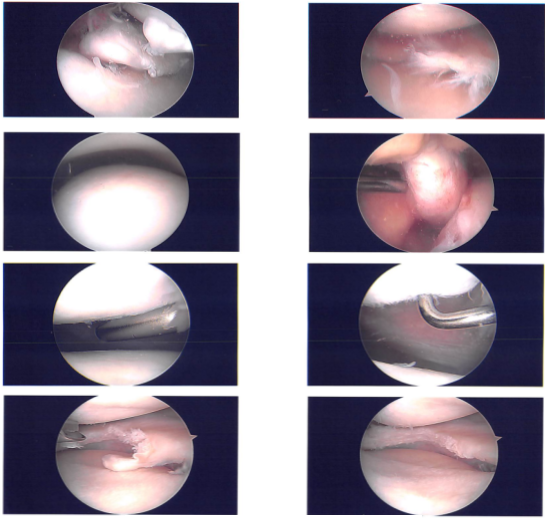

An arthroscopic entrance portal can be performed through a lateral entry portal. The user sat down inside the arthroscope. Grade 1 to grade 2 osteochondral lesions of the lateral aspect of the patella were discovered during a patellofemoral examination.

A medial meniscus tear was evident upon examination of the medial compartment. A spinal needle was used to create a medial entrance hole. When the probe was inserted, an evaluation of the medial meniscus tear revealed a lateral border tear with a flap.

The root remained unaffected, however there was a tear that went all the way to the posterior horn. The choice was made to remove the medial meniscus. Biters were used to conduct the medial meniscectomy, then shavers. A favorable margin was attained.

An intact ACL was visible upon examination of the left intercondylar notch. Both the lateral meniscus and the lateral femoral cartilage were seen upon examination of the lateral compartment. Additionally entered was the medial femoral cartilage.

A grade 1 to grade 2 osteochondral lesion was discovered during the patellofemoral examination and was removed with a razor. The medial entrance portal was used to insert the arthroscope, which was then used to balance the medial meniscus and perform chondroplasty using the shaver.

Final images were captured and stored. It was irrigated and drained completely on the knee. #4-0 nylon was used for the closure. The knee was then injected with 9 cc of 0.5% Naropin and 40 mg of Depo-Medrol. ABD, Webril, Xeroform, and Ace wrap were used for dressing. The patient was transported to recovery in stable condition after being extubated.